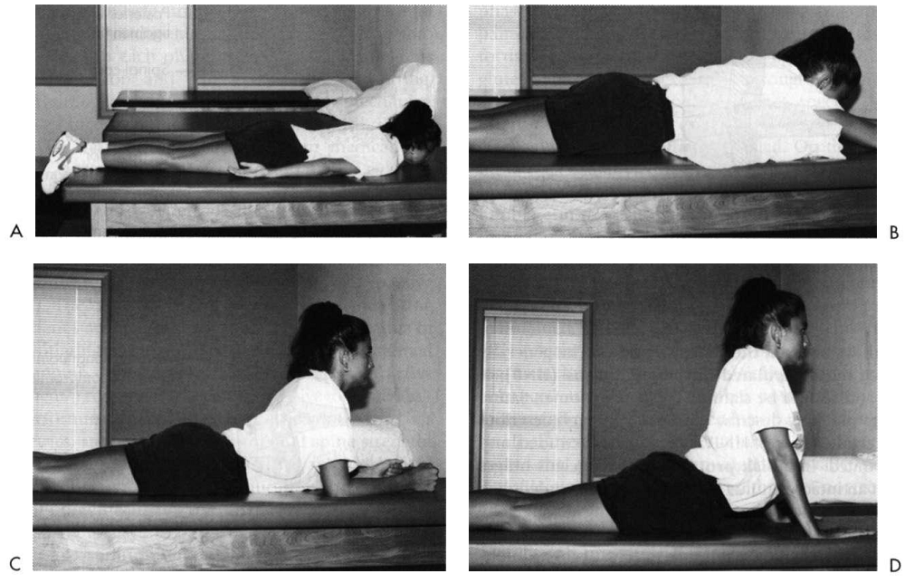

- Chương trình tập McKenzie:

Chương trình tập Mc Kenzie chủ yếu dựa trên các tư thế duỗi, nhằm mục đích giảm đau cấp tính và điều chỉnh tình trạng thoát vị của đĩa đệm, dự phòng tái phát ở các bệnh nhân thoát vị đĩa đệm trung tâm hoặc sau-bên.

Xem bài: Chương trình tập luyện Mc Kenzie